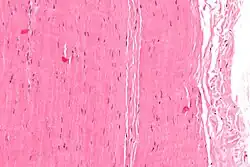

Micrograph of a piece of tendon; H&E stain | |

A tendon is made of dense regular connective tissue, whose main cellular components are special fibroblasts called tendon cells (tenocytes). Tendon cells synthesize the tendon's extracellular matrix, which abounds with densely-packed collagen fibers. The collagen fibers run parallel to each other and are grouped into fascicles. Each fascicle is bound by an endotendineum, which is a delicate loose connective tissue containing thin collagen fibrils[3][4] and elastic fibers.[5] A set of fascicles is bound by an epitenon, which is a sheath of dense irregular connective tissue. The whole tendon is enclosed by a fascia. The space between the fascia and the tendon tissue is filled with the paratenon, a fatty areolar tissue.[6] Normal healthy tendons are anchored to bone by Sharpey's fibres.